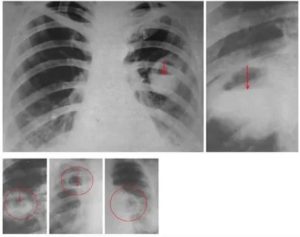

Когда абсцесс находится в процессе прорыва гнойника в области бронхов, на снимке с рентгена можно увидеть следующие изменения:

- стенки полости становятся гораздо тоньше;

- в центре пораженной зоны присутствует просветление, где имеется горизонтальный уровень жидкости;

- выше имеющегося уровня жидкости присутствуют области с некрозом тканей;

- по причине воспаления по гнойному типу внешняя сторона капсулы становится не такой четкой.

Рентгенологические признаки в стадии распада (прорыва абсцесса в бронхи) отличаются более выраженной картиной, позволяющей определить полость с уровнем жидкости, увидеть газ, расположенный над жидкостью в виде осветленного полукруга.

Для выявления размеров и расположения полостей снимки рекомендуется делать в нескольких стадиях наполнения плевральной полости жидкостью, например, до и после отхаркивания и в нескольких проекциях. Полость абсцесса на рентгенологических снимках чаще всего имеет овальную форму.

Таблица 2: Данные рентгенографии при легочном абсцедировании:

Этап заболеванияХарактеристика R-картины

До прорыва в бронх

Гомогенное затемнение размером 10-50 мм и более в полости легкого

В момент прорыва

Просветление в центре полости, определение в нем уровня жидкости с четким горизонтальным уровнем. Также может визуализироваться гнойная капсула.

После прорыва

Просветление, соответствующее размерам полости на фоне четкого отграниченного затемнения.